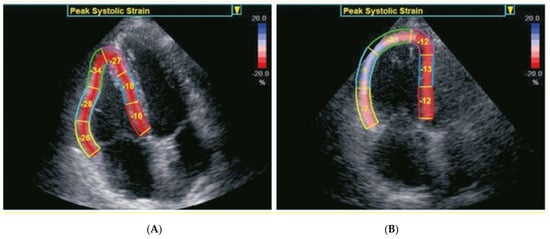

| RV basal wall LS (%) | −21.5 ± 7.9 | −20.8 ± 8.3 | 0.25 |

| RV middle wall LS (%) | −21.5 ± 8.2 | −21.1 ± 8.3 | 0.52 |

| RV apical wall LS (%) | −15.7 ± 8.4 | −17.1 ± 7.9 | 0.04 |

| Average RV free−wall LS (%) | −20.0 ± 7.6 | −19.8 ± 7.8 | 0.7 |